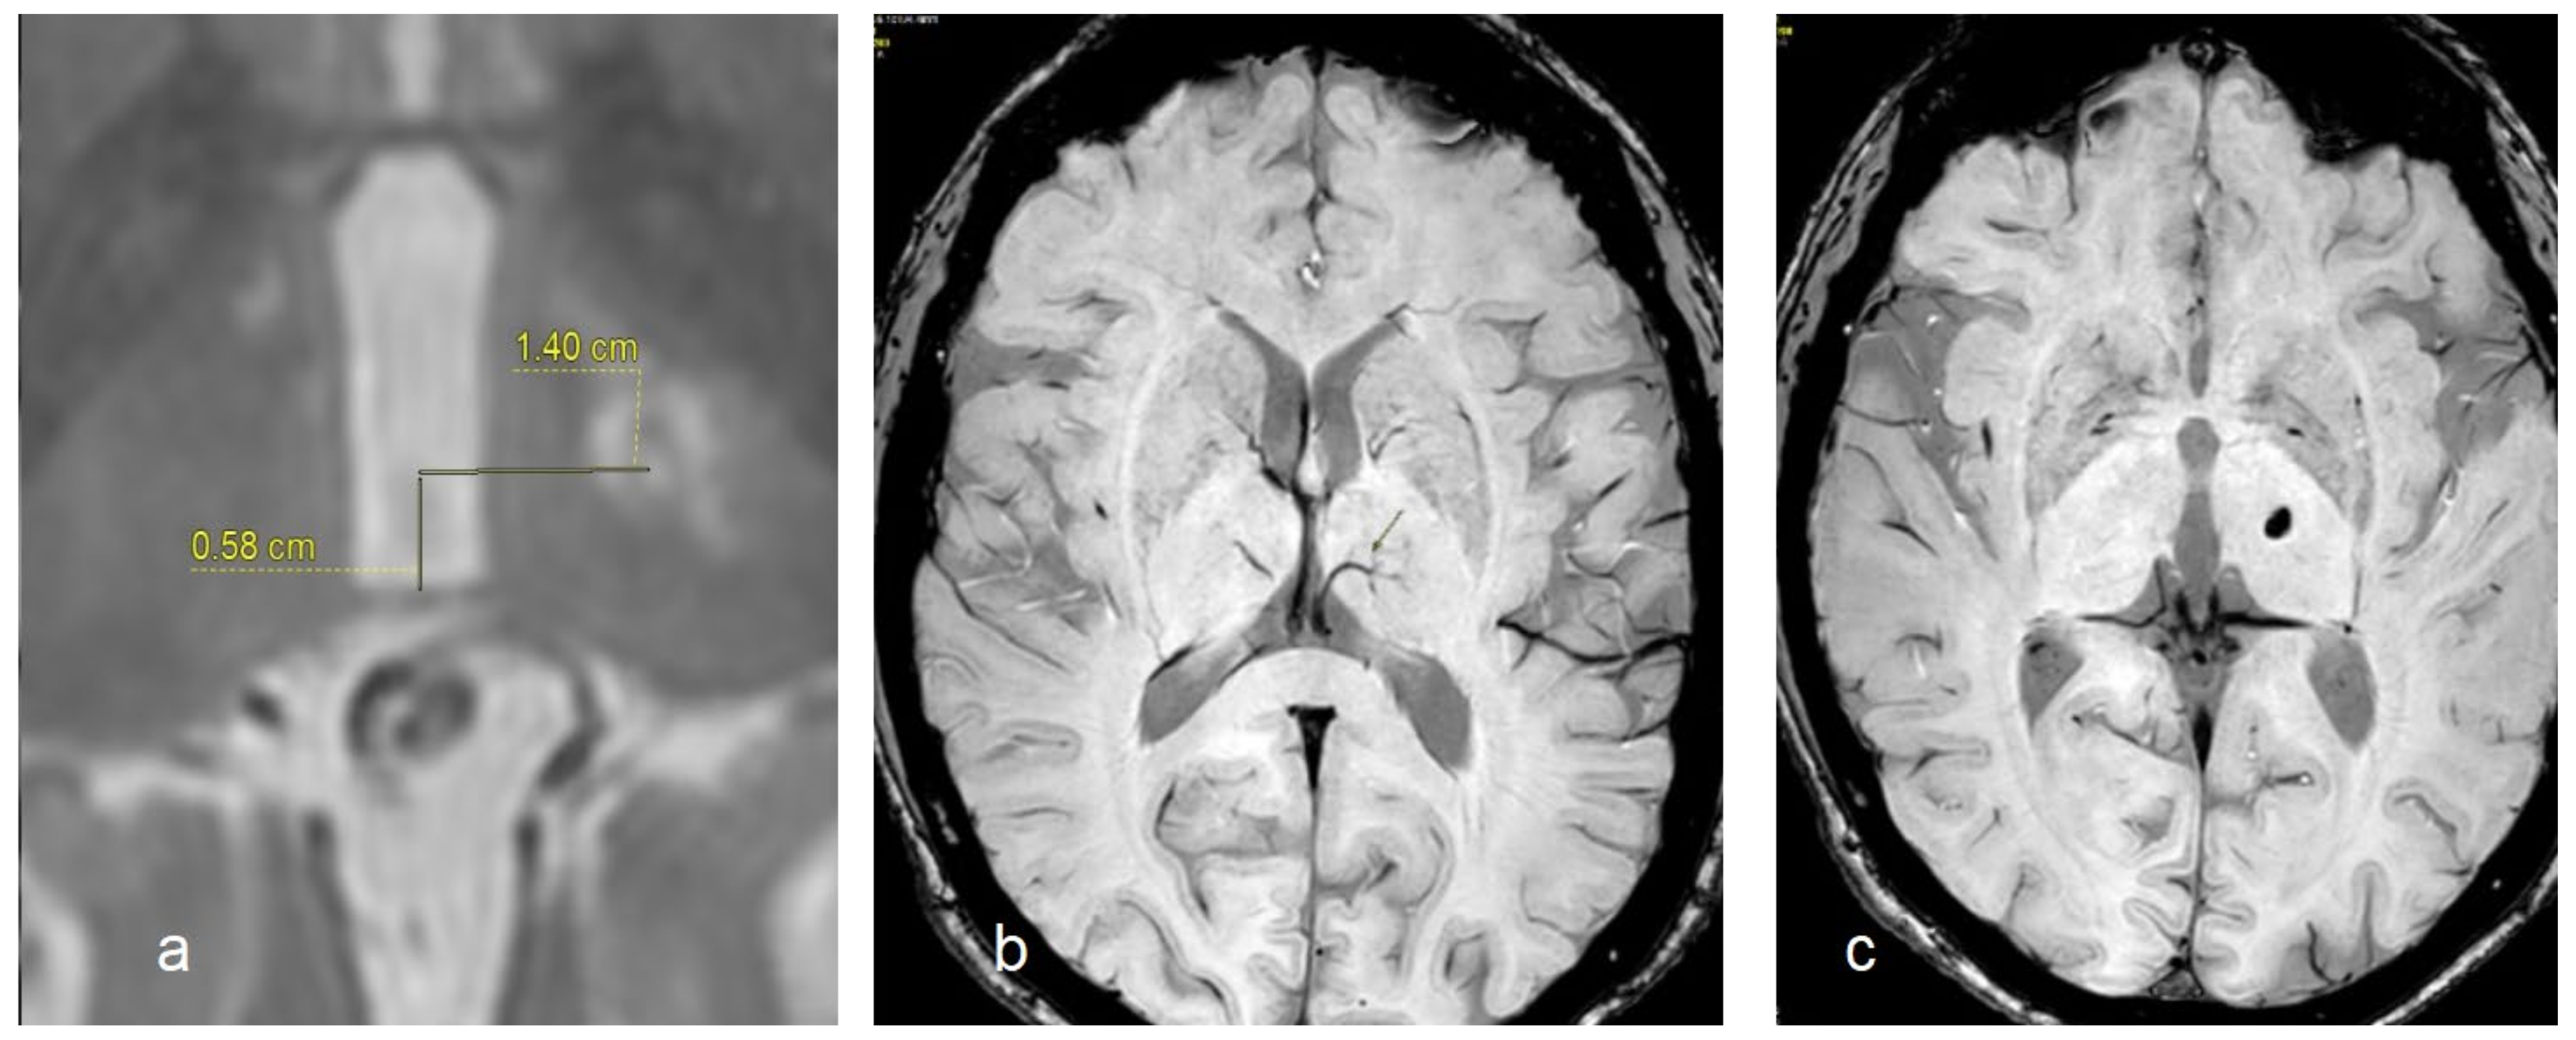

In Figure 1, we report a comparison of the target identification obtained by using stereotactic coordinates (a), STV identification (b), and the lesion of the target after sonication (c).

Figure 1.

Target identification by using stereotactic coordinates (a), STV visualization (the arrow indicates the vein) by using the SWI sequence (b), the real position of target obtained after sonication and evaluated after 4 weeks by using the SWI sequence (c).